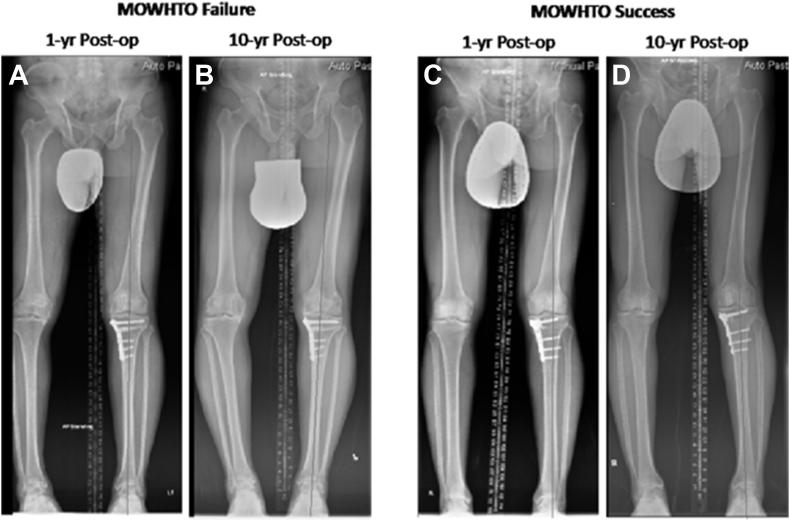

A total of 31 knees in these 22 cases were included. The follow-up rate was 100% at 13.4 ± 1.9 years (11-17). Mean age at time of surgery was 45.8 ± 9.5 years (18-53). At 10-year follow-up, four knees converted to require total knee arthroplasty (survival: 87.1%). Preoperative varus alignment with mechanical tibiofemoral angle of -9.26 ± 2.83 was corrected to 2.58 ± 2.46 after surgery and remained 2.01 ± 3.52 at the latest follow-up. Knee Society Knee Score increased significantly from 53.7 ± 11.1 preoperatively to 93.8 ± 6.8 at 1-year follow-up and 91.8 ± 9.7 at latest follow-up. Similarly, the functional score also increased significantly from 67.4 ± 21.0 preoperatively to 86.3 ± 14.5 at 1-year follow-up and 82.1 ± 16.6 at latest follow-up ( < 0.01). Whereas, the range of motion significantly decreased from 122.7 ± 6.6 preoperatively to 116.1 ± 15.5 at the latest follow-up.

这22例患者共纳入31个膝关节。随访率为100%,随访时间为13.4±1.9年(11 - 17年)。手术时的平均年龄为45.8±9.5岁(18 - 53岁)。在10年随访时,4个膝关节转为需要行全膝关节置换术(生存率:87.1%)。术前机械性胫股角为-9.26±2.83的内翻畸形在术后矫正至2.58±2.46,在末次随访时仍为2.01±3.52。膝关节协会膝关节评分从术前的53.7±11.1显著提高到术后1年随访时的93.8±6.8以及末次随访时的91.8±9.7。同样,功能评分也从术前的67.4±21.0显著提高到术后1年随访时的86.3±14.5以及末次随访时的82.1±16.6(P<0.01)。然而,活动范围从术前的122.7±6.6显著减小至末次随访时的116.1±15.5。